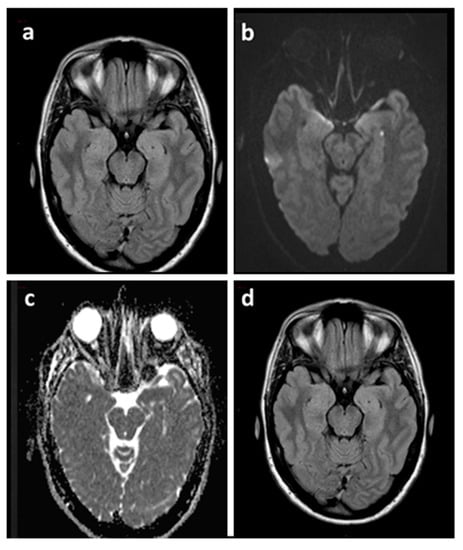

2.7.1. Magnetic Resonance Imaging (MRI)

- Lesions can be single or multiple and vary in size from 1 to 5 mm [7].

- In a recent meta-analysis of 1732 patients with TGA the pooled incidence of right, left, and bilateral hippocampal lesions were 37% (95% CI, 29–44%), 42% (95% CI, 39–46%), and 25% (95% CI, 20–30%), respectively [9].

- In the same study, DWI with a slice thickness ≤3 mm showed a higher diagnostic yield than DWI with a slice thickness >3 mm [63% (95% CI, 53–72%) vs. 26% (95% CI, 16–40%), p < 0.01] and there was no significant difference in the diagnostic yield between 3 T and 1.5 T imaging [pooled diagnostic yield, 31% (95% CI, 25–38%) vs. 24% (95% CI, 14–37%), p = 0.31)] [9].

- Focal hippocampal DWI lesions generally resolve 7–10 days after onset of TGA, with no long-term structural changes [58]. This complete reversibility of DWI hippocampal hyperintensity without structural sequelae, as confirmed by the lack of persistent signal change on T2-weighted or FLAIR sequences, does not conform to the time course of classic ischemic lesions [9].

- T2-weighted and FLAIR sequences allow us to identify and evaluate the extent of cerebral microangiopathy in order to provide a measure of the presence and degree of chronic hypertension [25]. In this way, these sequences can provide useful indications for a more rigorous antihypertensive drug treatment in patients with chronic hypertension and can help to calculate the risk of subsequent TGA recurrence in patients without microangiopathic alterations (for details see paragraph 3.1 of this review).

- Complementary imaging studies combining MRI and focal MR spectroscopy (MRS) of CA1 DWI/T2 lesions revealed a transient lactate peak without changes of N-acetyl-aspartate (NAA) and creatine (Cr), indicating acute metabolic stress of CA-1 neurons during TGA [58]. The lactate peak was detected only in the DWI lesion and not in the perifocal tissue, suggesting that the metabolic changes in CA1 neurons were highly focal and not suggestive of a globally altered metabolic status in the hippocampus [58] (see Part I of this review for the pathogenetic implications of these neuroradiological findings).